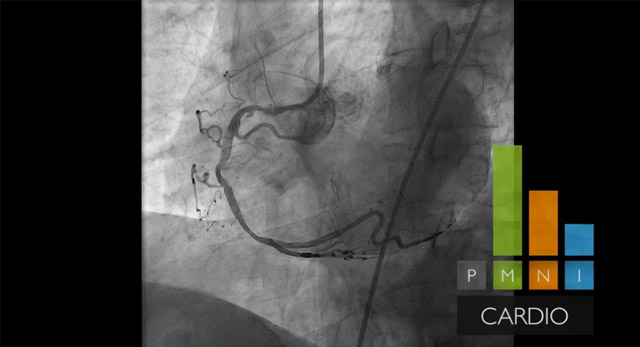

يمكن أن يشكل استخدام الأشعة السينية وتقنيات التصوير ثلاثي الأبعاد بالموجات فوق الصوتية وتفسيرها أثناء إجراءات علاج أمراض القلب الهيكلية (SHD) تحديًا، وخاصة عند توجيه مسابر القسطرة التي تحمل الأجسام المزروعة.

وبالتالي، يساعد الوصول السهل والسريع إلى الرؤية المحسنة والتنقل عبر المقاطع التشريحية للأنسجة الرخوة باستخدام التوجيه بالصور المباشرة في تحديد المسار الأمثل للعلاج بعد التوصل إلى التشخيص الصحيح الموثوق.